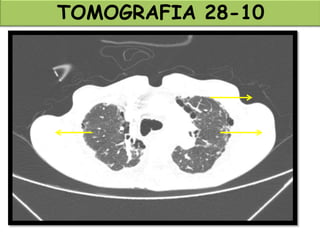

TOMOGRAFIA 28-10